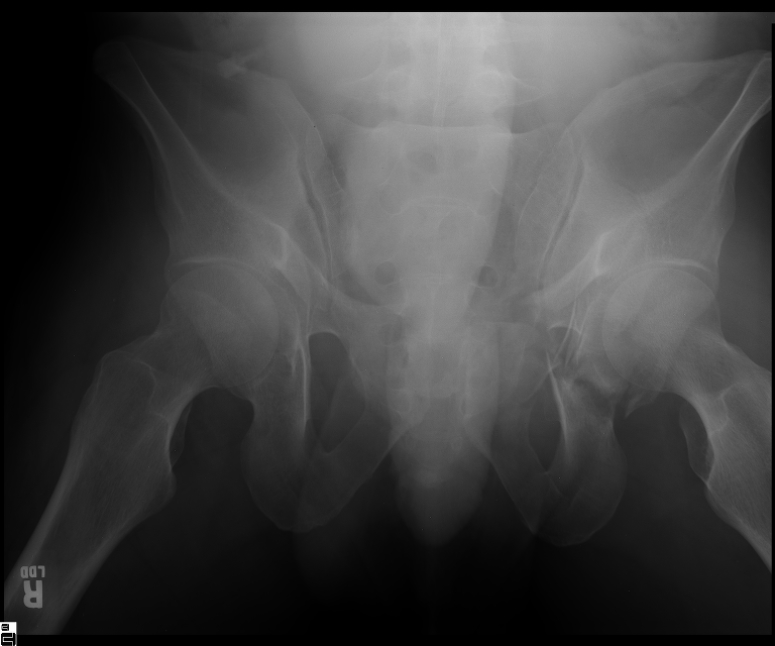

25 yo brittle diabetic, became hypoglycemic and passed out on his motorcycle. Sustained bilateral lateral Hoffa fractures with associated LCL injury on the right and right distal radius fracture. I have questions regarding his pelvic ring/acetabular fracture on the left. Appears to be a very low posterior column fracture with associated posterior wall, marginal impaction. Superior and inferior rami fractures as well on the left giving him a floating segment of inf ramus/ischium/posterior column, but no detectable posterior ring injury. Should the posterior column/posterior wall fracture be addressed surgically because of the marginal impaction? Or is this fracture low enough to be treated non-operatively? I appreciate the input.

It's an interesting case. The plain films show the impaction, but most of the joint looks pretty good. The CT cuts look awful, though.

The impaction is so big I don't think I would ignore it. It IS down low, but it takes up almost the whole southern hemisphere of his joint.